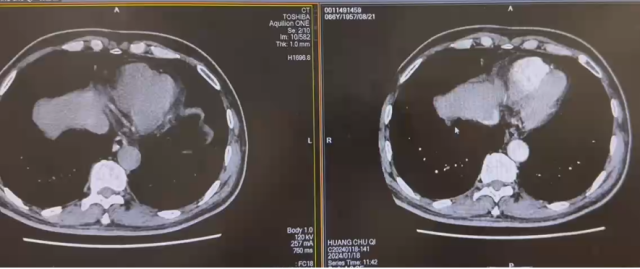

伏罗尼布+依维莫司新辅助靶向治疗

CT平扫+增强

检查诊断:

1.下腔静脉管腔较前缩小、充盈缺损较前略减少;

2.右肾静脉栓子同前;左肾静脉充盈缺损未见显示;双侧骼静脉充盈欠佳;

3.右肾上极病变同前:恶性肿瘤可能;右肾盂管壁增厚强化:受累?

4.盆腔少量积液;

5.右肝动脉起自肠系膜上动脉;左下肺动脉栓子;

日期:2024.3.3

CT 报告

1.下腔静脉管腔较前缩小、充盈缺损较前减少;

2.右肾静脉栓子较前减少;右侧髂总静脉内少许栓子;

3.右肾上极病变较前缩小,右肾孟管壁受累较前减轻;

4.盆腔少量积液较前减少;

5.左下肺动脉栓子形成,范围较2024-01-22日稍缩小;

双靶治疗(2个月)

双靶治疗(4个月)

2024.6.12 行根治性肾切除+腔静脉瘤栓取出术